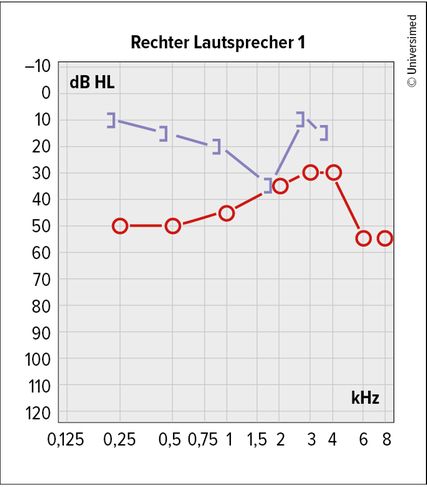

In der Tonaudiometrie liegt eine Schallleitungsstörung vor, oft mit der typischen Knochenleitungszacke bei 2kHz, der sogenannten „Carhart-Senke“. Dies kommt dadurch zustande, dass für eine optimale Bewegung der Innenohrflüssigkeit und somit Auslenkung der Basilarmembran in eben diesem Frequenzbereich um 2kHz der Stapes frei schwingen können muss. Ist dieser fixiert, wird eine scheinbare Innenohrhörminderung, die aber aufgrund fehlender Resonanz und nicht geschädigter Innenohrstrukturen entsteht, im Tonaudiogramm aufgezeichnet (Abb. 1). Diese Carhart-Senke verschwindet häufig wieder nach erfolgter Stapesplastik.4,5

In der Audiometrie zeigt sich das typische Bild einer Schallleitungsstörung mit „Carhart-Senke“. Im Verlauf kann es auch zu Innenohrabfällen kommen.